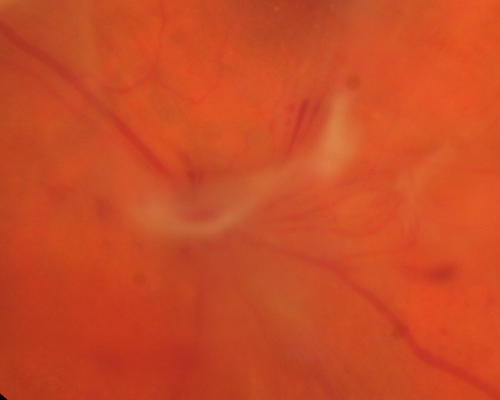

Proliferative Diabetic Retinopathy - Vitreous Hemorrhage and Tractional Retinal Detachment Left Eye

52-year-old man has been diabetic for nineteen years developed substantial vision loss over the last month or two. OD 20/70, OS 20/200.

Preretinal Fibrosis Left Eye